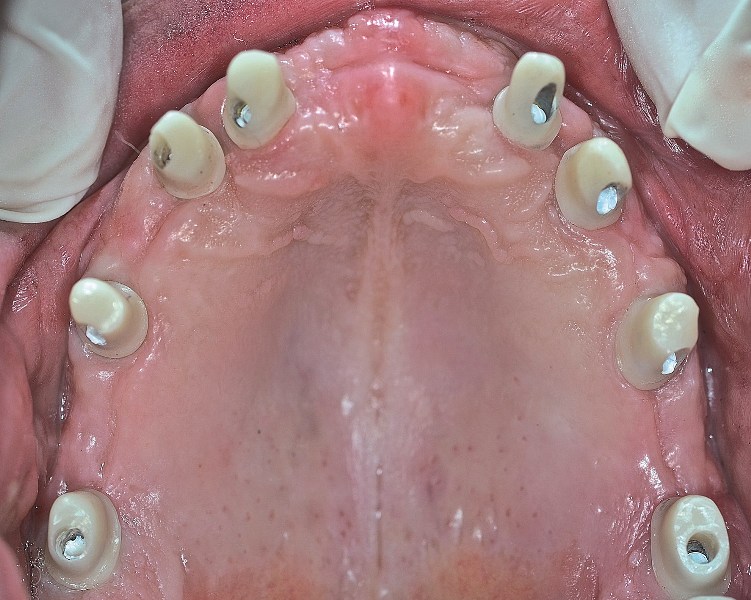

Dr Dariusz Srokowski: Implanty to rozwiązanie dla pacjentów mających braki w uzębieniu lub dotkniętych całkowitym bezzębiem, którzy spełniają określone warunki kostne. Decyzja o podjęciu i przebiegu leczenia zapada na podstawie wnikliwej analizy danych uzyskanych w badaniu pantomograficznym (zdjęcie panoramiczne) i tomograficznym (obrazowanie trójwymiarowe).

W mojej opinii, w naprawdę wyjątkowych przypadkach można umocować 12 zębów na stałe na 4 implantach. Warunki muszą być jednak bardzo sprzyjające. Aby wszczepić wystarczająco długie i szerokie implanty do utrzymania 12 zębów, kość musi być obfita. Bardziej realistyczną liczbą jest 5 do 8 implantów. Wówczas nie są one przeciążone, a siły zgryzu rozkładają się prawidłowo. Ostateczna ilość implantów przy pełnej rekonstrukcji to decyzja bardzo indywidualna i złożona. Składają się na nią  takie czynniki, jak jakość i ilość kości, tonacja mięśni twarzy, rozmiar szczęki i żuchwy pacjenta.

Pełna rekonstrukcja uzębienia jest jedną z najtrudniejszych procedur w stomatologii. Jeżeli odbudowa protetyczna uzębienia obejmuje także własne zęby pacjenta, to możemy wykorzystać korony, mosty i implanty występujące pojedynczo lub połączone w mosty. Pełną rekonstrukcję zaczynamy od wstępnej analizy jamy ustnej, modeli pacjenta stworzonych na podstawie wycisku, zdjęć rtg oraz tomografii. Na podstawie tych informacji wykonujemy projekt przyszłego uzębienia. Dalszy przebieg leczenia jest uzależniony od tego, jakie procedury należy wykonać, zanim możliwa będzie implantacja. Po wszczepieniu implantów następuje etap uzupełnień tymczasowych/próbnych, na podstawie których pacjent może ocenić estetykę i wygodę przyszłych uzupełnień stałych. Pacjent ma szansę zgłosić swoje uwagi do zaproponowanych uzupełnień stałych i uzyskać efekt końcowy, który go całkowicie ustatysfakcjonuje